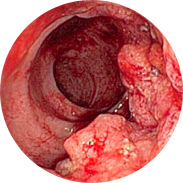

Inflamația și supurația mucoasei rectale

Sângerarea poate duce la apariția anemiei

O creștere a temperaturii corpului, cu inflamație severă, poate duce la febră

Și cel mai rău lucru este cancerul rectal!Studiile clinice pe scară largă ale Proctolax au fost efectuate la Centrul Medical Român (București) în 2016. În total, mai mult de 1000 de bărbați și femei cu hemoroizi de diferite grade au participat la studii. Toți subiecții au folosit crema Proctolax timp de 3 săptămâni. Chiar și medicii au fost uimiți de rezultatele studiului!